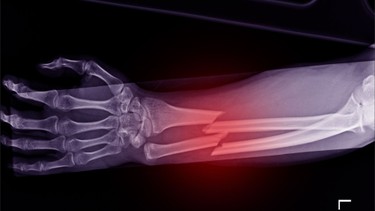

Phương pháp này thường được áp dụng cho các trường hợp gãy ít di lệch hoặc không di lệch. Sau khi đánh giá bằng hình ảnh như X-quang, CT… bác sĩ sẽ nắn chỉnh và cố định tay bằng bột hoặc nẹp trong thời gian phù hợp. Trong quá trình điều trị, người bệnh cần tái khám định kỳ để kiểm tra tình trạng liền xương và phát hiện sớm nguy cơ di lệch thứ phát.

Điều trị can thiệp chỉnh hình